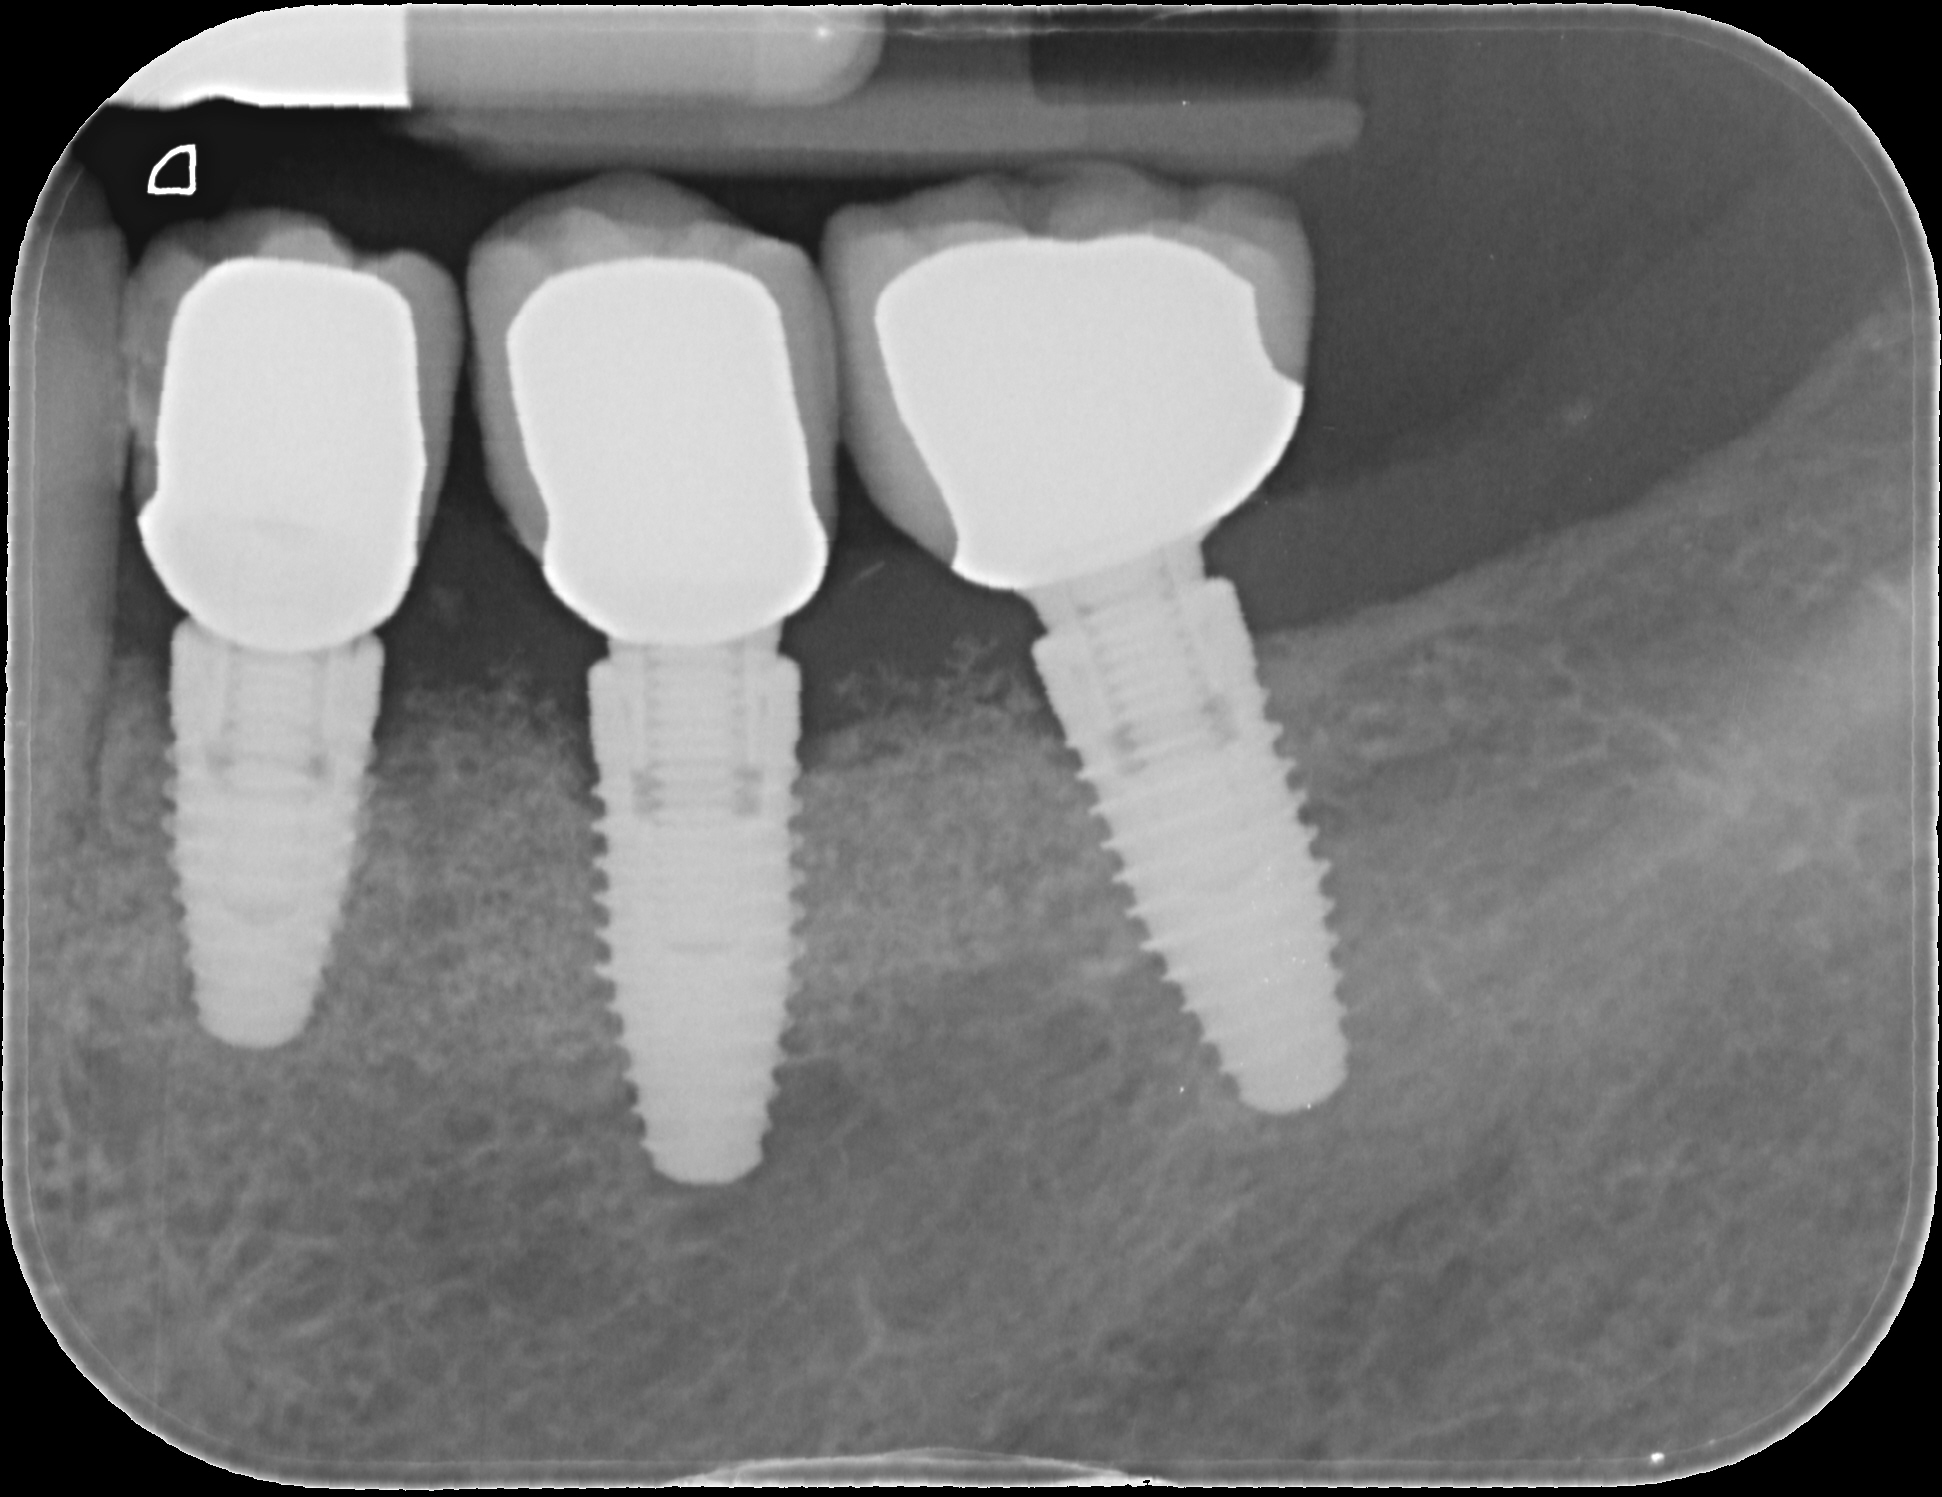

A 52-year-old patient is a referral and has been wearing an immediate provisional partial denture after replacement of her worn and fractured fixed partial denture. As a definitive treatment solution, the patient desired "beautiful and long-lasting" implant-supported single crowns. Clinically the CT-scan revealed a very narrow bone crest ("knife-edge") in the 3rd quadrant. Implant placement has been planned with a simultaneous GBR procedure.